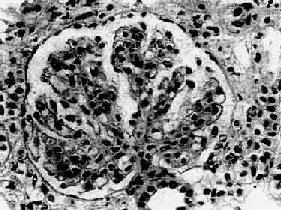

图12-13 膜性增生性肾小球肾炎

肾小球系膜细胞增多,增生的系膜组织侵犯毛细血管,毛细血管壁增厚,腔狭小,肾小球丛呈分叶状